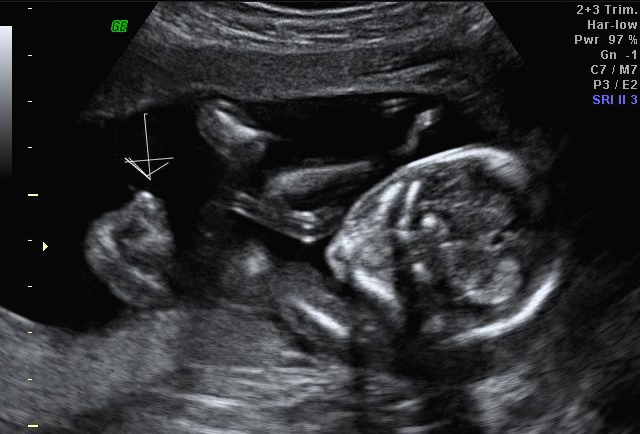

일주만에 더 커있는 우리 트롱이~ 어찌나 꼬물꼬물 귀엽게 움직이던지 ㅎㅎ 트롱이 건강상태를 확인 후 다시 성별을 확인했는데 100프로 아들이라며 지금 병원에서 일을 하시고 경력이 25년 됐다고 믿음을 확실히 주셔서 초음파 검사가 끝나고 바로 부모님께 연락을 드리고 아들 옷 사러 갔어요 ㅋㅋㅋ

아 진짜 전문가는 다르구나~ 이렇게 이른 주수에도 성별을 알 수가 있구나 생각을 했지만 이 시기 때는 성별을 정확히 알 수 없다는 글들을 봐서 살짝~ 의심스럽기도 했지만 그래도 100프로라니깐 ㅎㅎ 믿어보았어요~ 근데 위에 사진을 보면 성별을 알 수 있는 각도 법이 있는데 각도가 딸 같아서 긴가민가~하긴 했지만 의심은 잠시! 전문가 분을 믿기로 ㅋㅋㅋㅋ